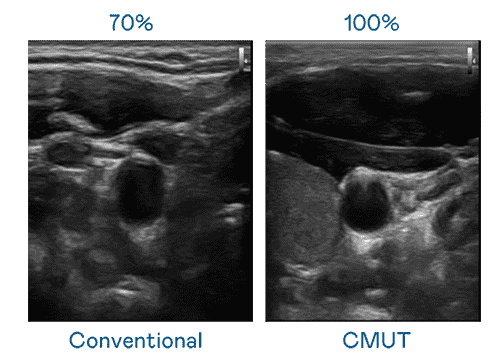

CMUT 技术是一种用电容式微机电元件来产生超音波讯号的技术。。。与传统 PZT 压电式技术相比,,,,CMUT 频宽增加 30%,,更宽频的超音波讯号让影像解析度大幅提升,,,是实现高影像品质医疗超音波扫描、、、、促进精准医疗发展的关键技术。。。。

大频宽带来超清晰影像

超音波影像的解析度高低,,,,首先取决于探头能发出的讯号频宽。。。。Wepay CMUT 可提供高清晰的超音波讯号,,,,提供高频宽、、高灵敏度、、、、影像纹理细节更高的超音波影像,,,,协助医护人员缩短影像判读时间及利用精准的医疗影像进行诊断。。。。